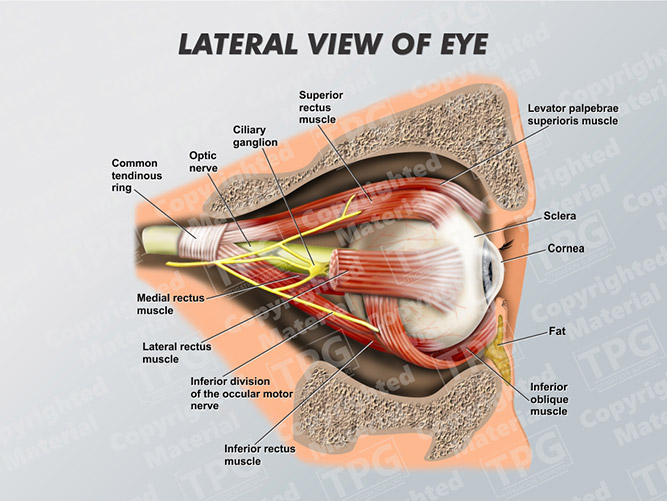

Anatomy Of The Eye - Lateral View - TrialExhibits Inc.

www.trialexhibitsinc.com

www.trialexhibitsinc.com

lateral anatomy

Eye Lateral - Order

presentationgroup.com

presentationgroup.com

eye lateral